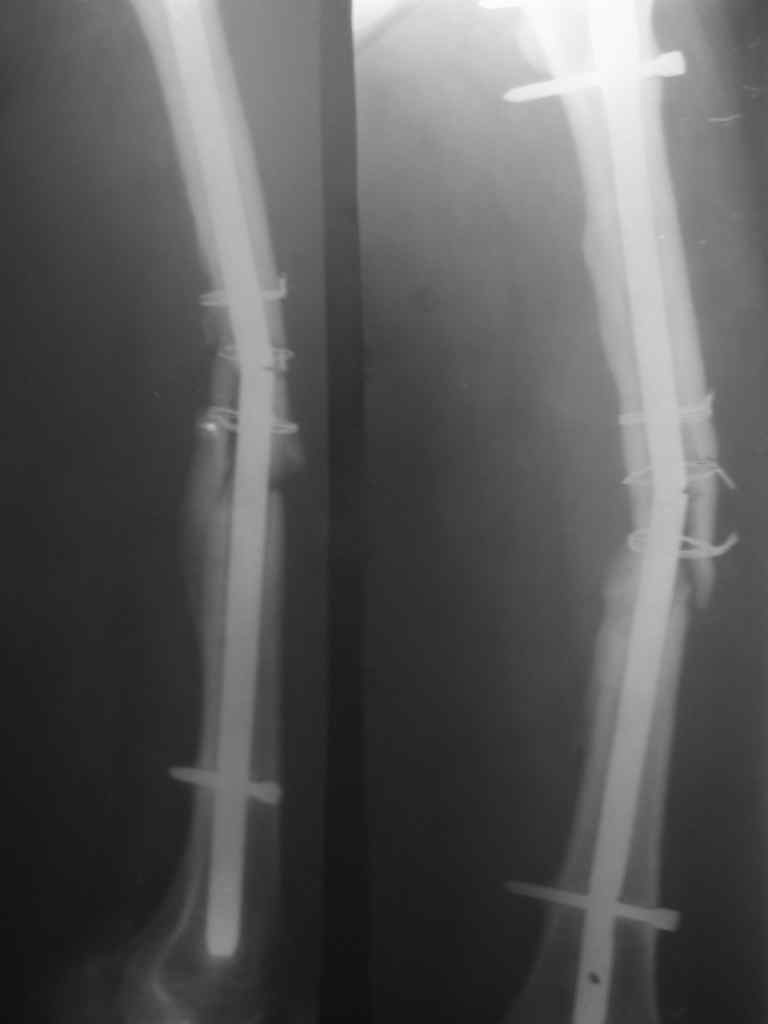

Перелом стержня, серкляж

Поступила молодая,маленькая девочка 18 лет с болями в левом бедре. Из истории:автодорожная травма в ноябре 2005 года, тогда же оперировалась данным способом. Проживает в селе и как правило в таких случаях выпала из поля зрения ведущего доктора.

По нашему мнению возможен реостеосинтез штифтом с рассверливанием более большого диаметра.Но возникают вопросы:

1.Убирать серкляж или нет если получится удалить отломки ChM закрыто.

2.Устранять деформацию бедра АВФ этапно или сразу одномоментно в ДРУ.

3.Блокирование - статическое или динмическое (либо статику на месяц а потом динамизация?)

4.Вопрос о костной пластике и туннелизации.

Ноябрь 2005г. и 18 лет это не 6-8мес это год. на последних снимках разве мы видим элементы "ЗДОРОВОЙ" консолидации сдесь должна быть серьезная гипертрофическая мазоль.